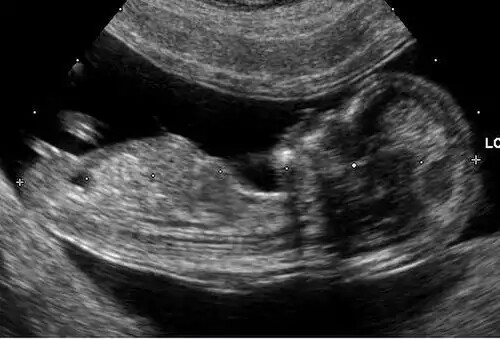

سونوگرافی ( به فرانسوی: sonographie ) یا فراصوت نگاری یکی از روش های تشخیص بیماری در پزشکی است. به این روش اکوگرافی، پژواک نگاری و صوت نگاری نیز گفته می شود. این روش بر مبنای امواج فراصوت و برای بررسی بافت های زیرجلدی مانند عضلات، مفاصل، تاندون ها و اندام های داخلی بدن و ضایعات آن ها پی ریزی شده است. سونوگرافی در حاملگی نیز کاربردهای وسیعی دارد. همچنین امروزه سونوگرافی کاربردهای درمانی نیز دارد.